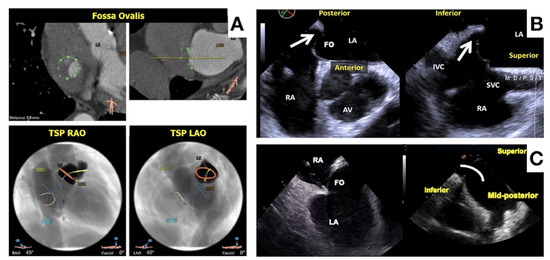

- Fukutomi, M.; Fuchs, A.; Bieliauskas, G.; Wong, I.; Kofoed, K.F.; Søndergaard, L.; De Backer, O. Computed tomography-based selection of transseptal puncture site for percutaneous left atrial appendage closure. EuroIntervention 2022, 17, e1435–e1444. [Google Scholar] [CrossRef]

- Wang, D.D.; Eng, M.; Kupsky, D.; Myers, E.; Forbes, M.; Rahman, M.; Zaidan, M.; Parikh, S.; Wyman, J.; Pantelic, M.; et al. Application of 3-Dimensional Computed Tomographic Image Guidance to WATCHMAN Implantation and Impact on Early Operator Learning Curve: Single-Center Experience. JACC Cardiovasc. Interv. 2016, 9, 2329–2340. [Google Scholar] [CrossRef]